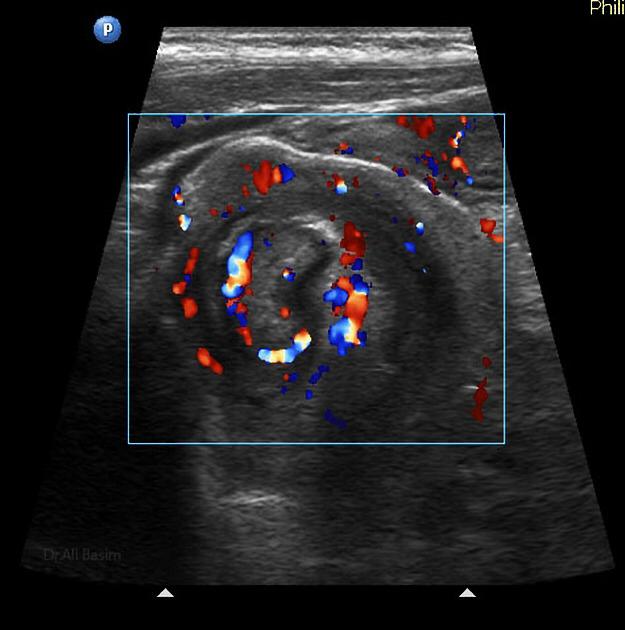

La invaginación intestinal es la causa más común de obstrucción intestinal en niños de 3 meses a 3 años. Se caracteriza porque un segmento de intestino penetra en otro segmento intestinal. Puede presentarse en colon, intestino delgado o entre intestino delgado y el colon. El resultado es la obstrucción intestinal.